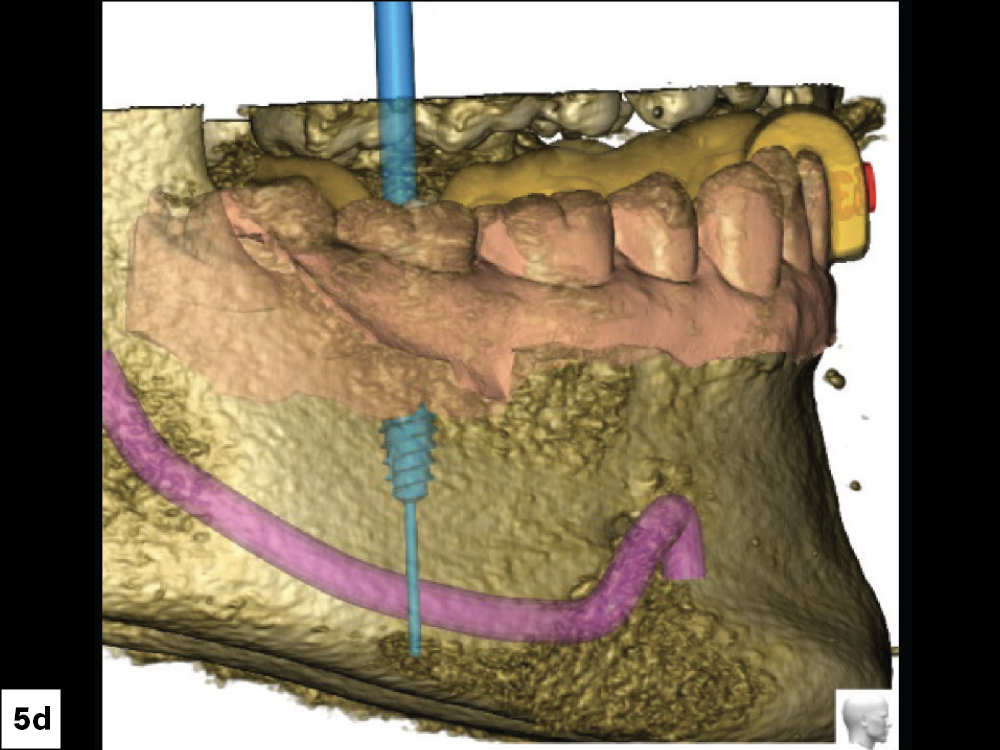

In-office milling is a quickly evolving option for the modern dental practice. With the introduction of a same-day screw-retained option, BruxZir® NOW SRC milling blocks, there’s even more opportunity for optimizing single-unit restoration workflows. In this case study, I’ll demonstrate how this product can be used as part of an efficient workflow for tooth replacement in the posterior. When combined with guided surgery and in-office crown design, this procedure offers reliable results while saving money and significantly cutting down on chair time for dentists.